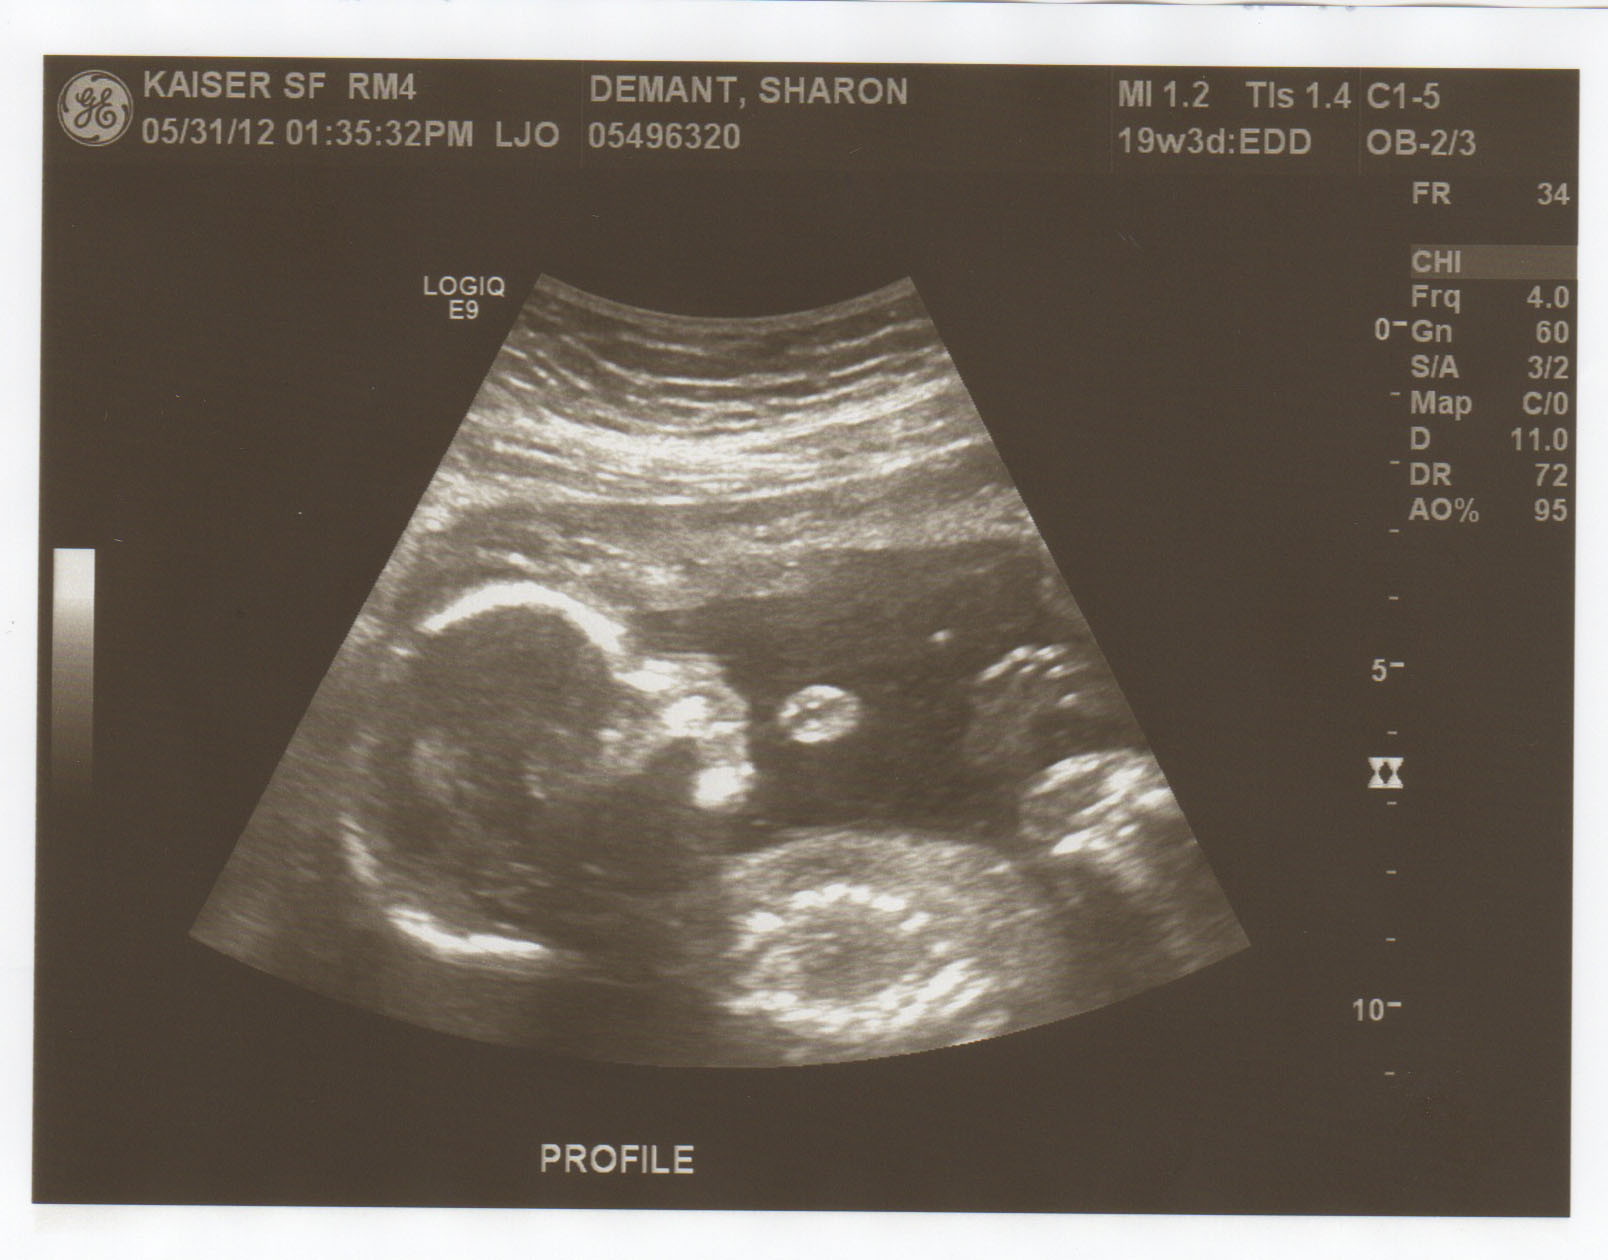

It’s hard to believe we were still residents of South Korea a little over 3 months ago. We have changed virtually every aspect of our lives since then; Jason works full time while I am now the Housewife, we live in a city where we can communicate without circus gestures, we have carpeted floors in our apartment, our shower is a separate entity from the bathroom as a whole, we’re expecting our first baby (girl) in October, and most importantly… we have a garbage disposal.

You heard right. The first baby Demantski is on its way! Conceived while we were still in Korea, and now a resident of the worldy city of San Francisco, this unborn baby girl is already more cultured than most adults. I’m guessing she will be eating kimchi at one week old and will be reading “The Ramayana” as she exits my womb.